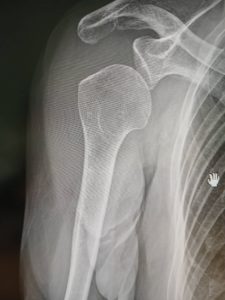

今回のケース(80代女性)

•明確な外傷の記憶なし

•後から思い返すと、自宅で数回転倒していた可能性あり

•徐々に肩の痛みが強くなり、箸も持てない日が出現

病院を2か所受診し、どちらも

「レントゲン異常なし」「経過観察」

しかし、当院で改めて状態を確認すると

•肩の可動域は大きく制限

•動かすと強い運動痛

•画像上、上腕骨頭の位置異常(下方偏位)

この時点で、

腱板損傷・部分断裂、もしくは亜脱臼の可能性を強く疑いました。

最終的に別の整形外科では

「肩の亜脱臼(高齢者によくある)」との診断。